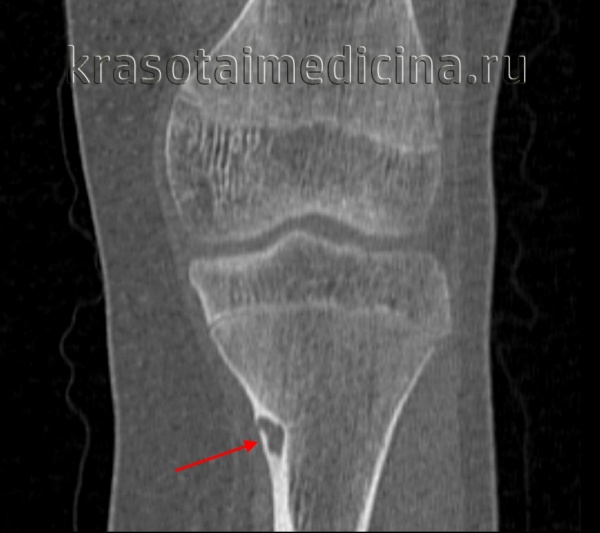

- Рентгенография кости. На снимках визуализируется кистообразные изменения или неоплазия в виде «мыльных пузырей» в метафизарной зоне. Признаки общего остеопороза отсутствуют, вокруг измененного участка может просматриваться остеосклероз. Границы доброкачественной ГКО более четкие, но из-за местно-агрессивного роста при значительном размере возможно появление «костного козырька». Выраженная периостальная реакция нехарактерна. Злокачественная остеокластома имеет нечеткую структуру. На снимках рано обнаруживается разрушение кортикального слоя.

- КТ и МРТ кости. Компьютерная томография дает более четкое представление о форме, размерах, границах гигантоклеточной опухоли, в сомнительных случаях позволяет подтвердить или опровергнуть разрыв коркового слоя. В ходе магнитно-резонансной томографии исследуют интрамедуллярный и кистозный компоненты, оценивают состояние окружающих мягких тканей, расположение сосудов и нервов. Методики помогают выбрать оптимальный вариант хирургического вмешательства, спланировать операцию.

Гигантоклеточная опухоль кости (ГКО, остеобластокластома, остеокластома) – неоплазия с двумя клиническими вариантами течения. Данные о распространенности существенно разнятся – от 4 до 25% от общего количества опухолевых поражений скелета. Доля злокачественного варианта составляет 5-10%. 80% пациентов находятся в возрастной категории 20-50 лет, пик заболеваемости приходится на третье десятилетие жизни. Женщины страдают несколько чаще мужчин. В 50-65% случаев поражается область коленного сустава (дистальная часть бедра или проксимальная часть голени).

В 89% ГКО формируется в длинных трубчатых костях. Нижние конечности поражаются двое чаще верхних. Первое место по распространенности занимает дистальный метафиз бедра, второе – проксимальная часть большеберцовой либо малоберцовой кости, третье – периферические отделы луча, четвертое – дистальная часть большеберцовой кости. Позвонки, мелкие и плоские кости страдают редко.

Характерны одиночные очаги, в литературе также описываются отдельные двойные локализации, чаще расположенные близко друг к другу в сочленяющихся костях. Гигантоклеточная опухоль находится в метафизе, иногда растет в сторону диафиза. Первично диафизарное расположение выявляется крайне редко. Одноядерные клетки новообразования имеют сходство с остеобластами, гигантские многоядерные – с остеокластами. В ткани неоплазии выявляются костные балочки, включения остеоида.